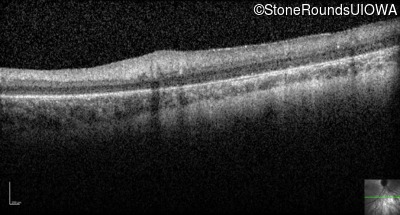

Optical Coherence Tomography - Left -

No Light Perception

Exemplar

Expanded OCT Stack

×